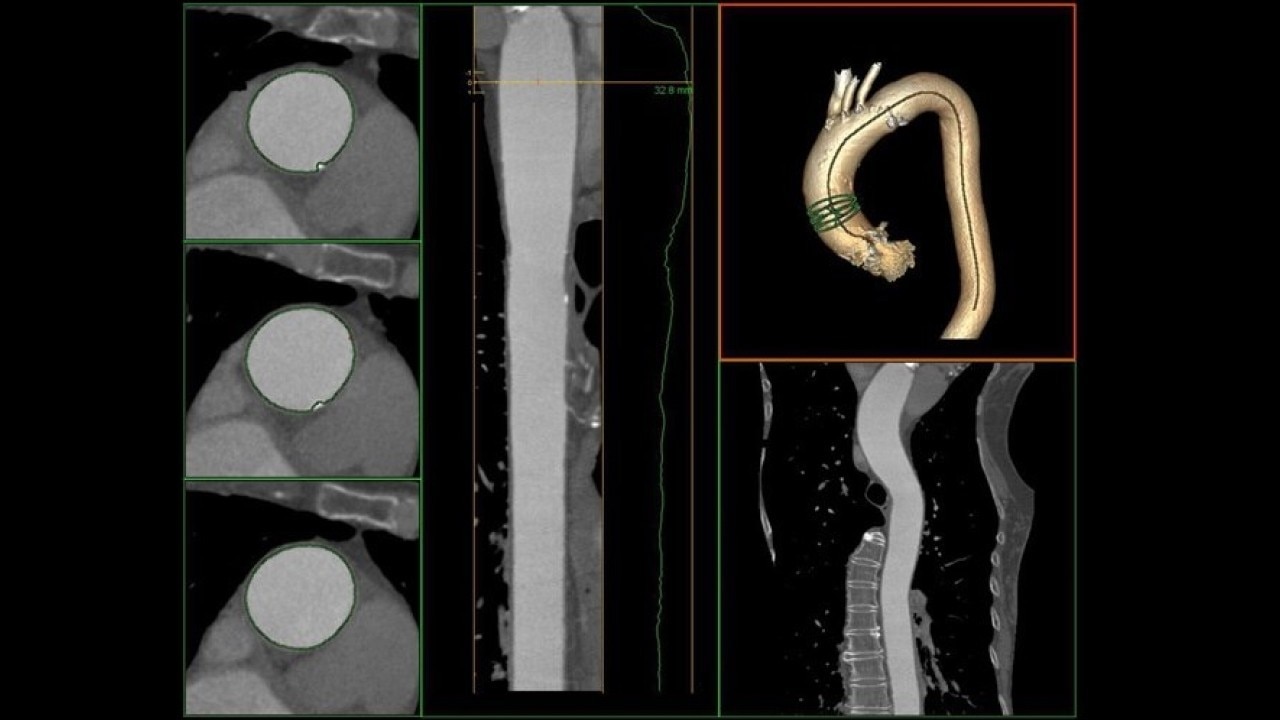

The Valve Planning protocol in the VesselIQ Xpress application lets you visualize cardiac anatomy with the degree of detail required to evaluate the presentation of the aortic valve. Armed with this information, you can develop a pre-procedural TAVR/TAVI plan to establish a therapy strategy for the patient.